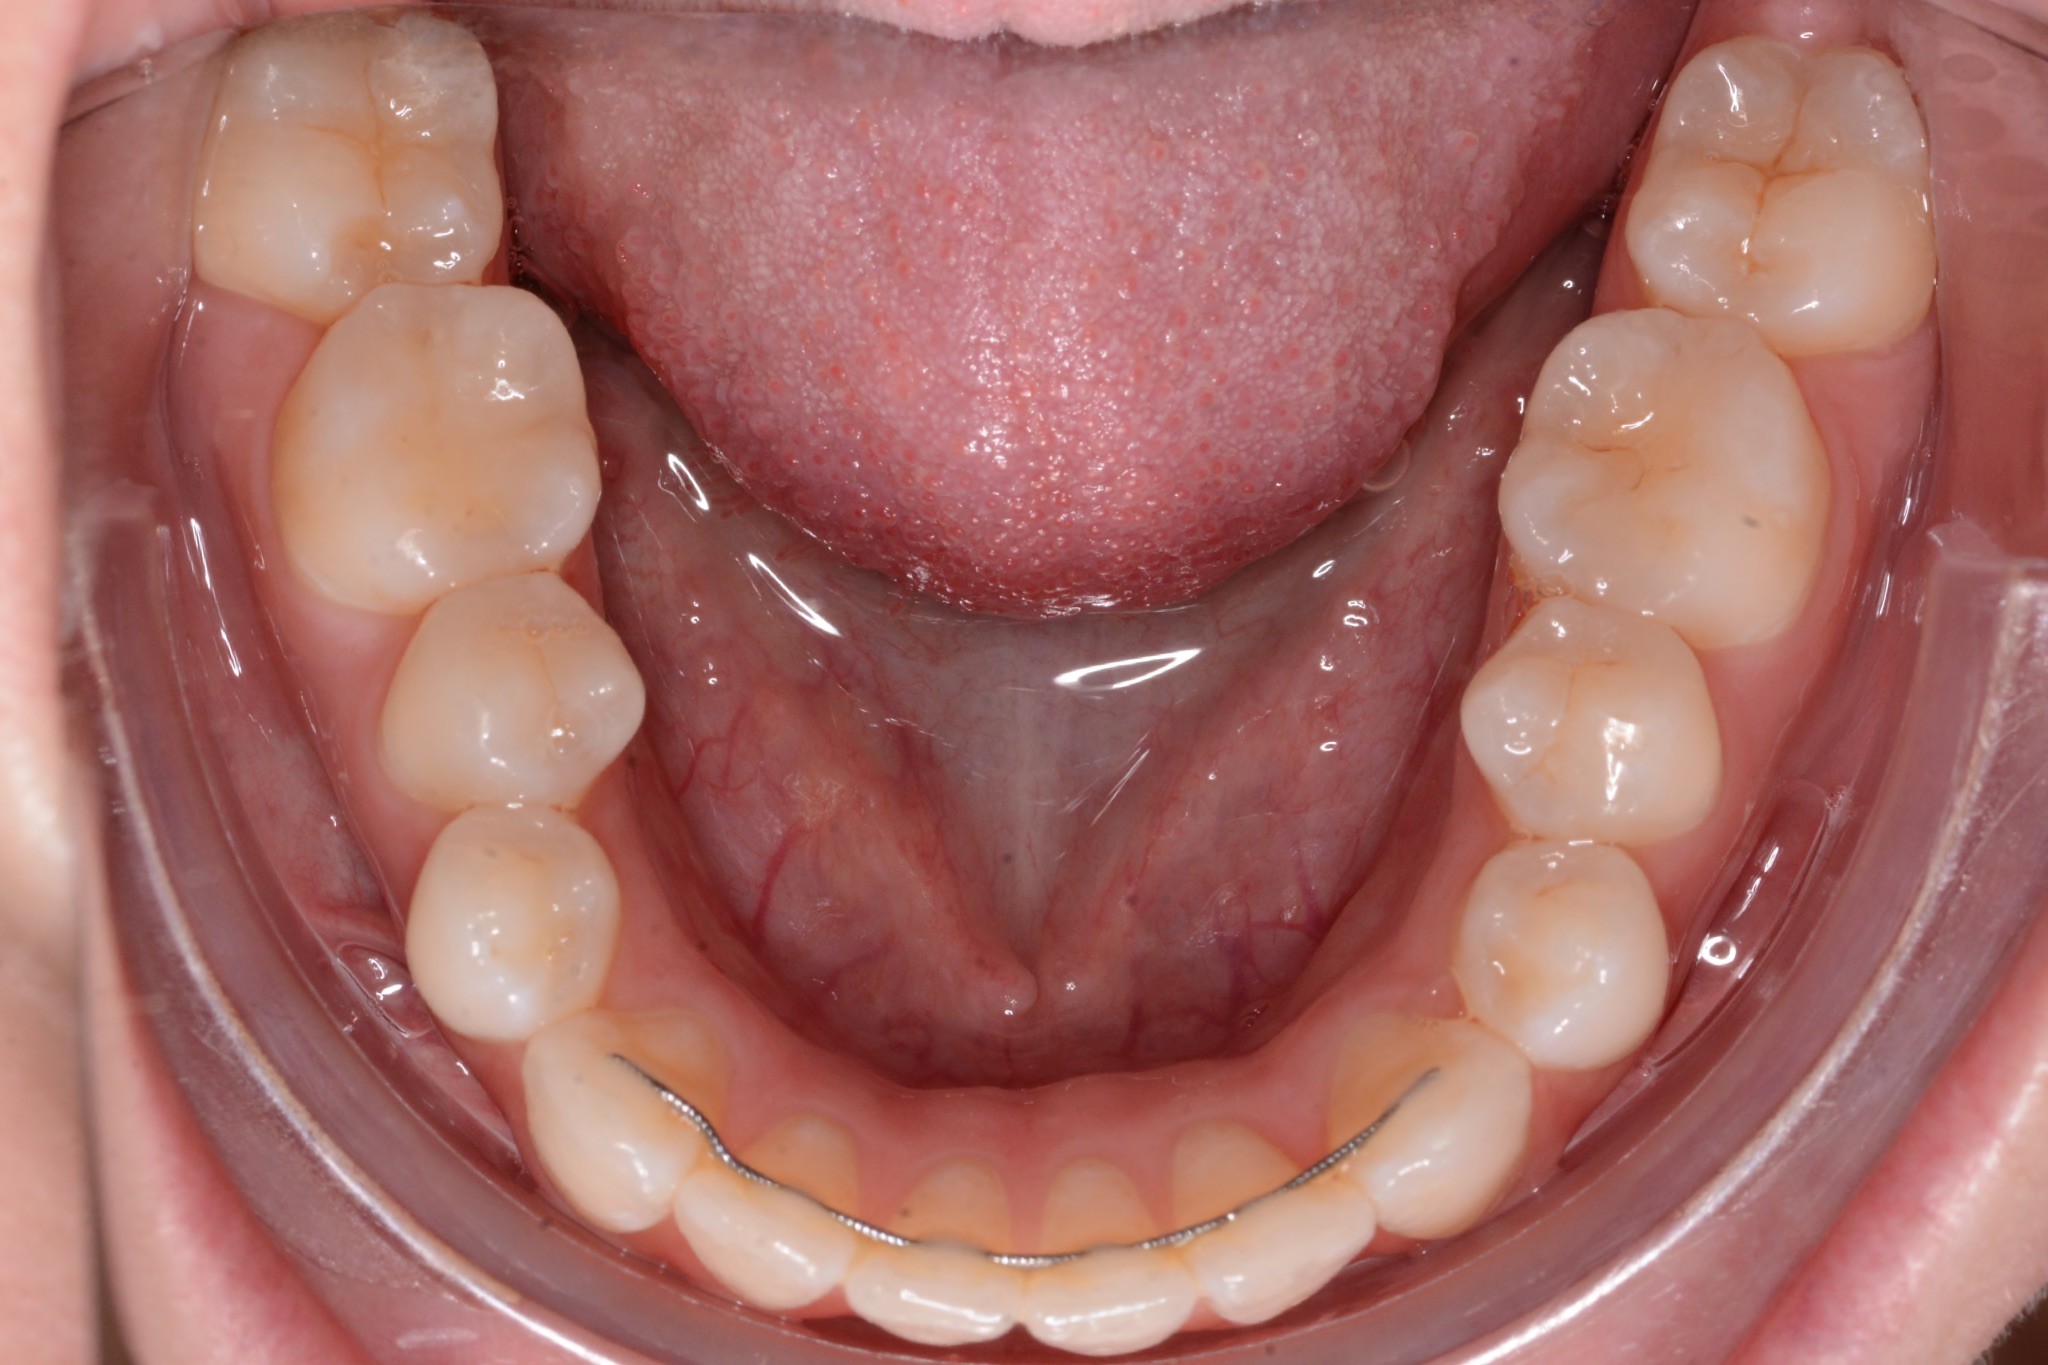

Final results

INTRAORAL